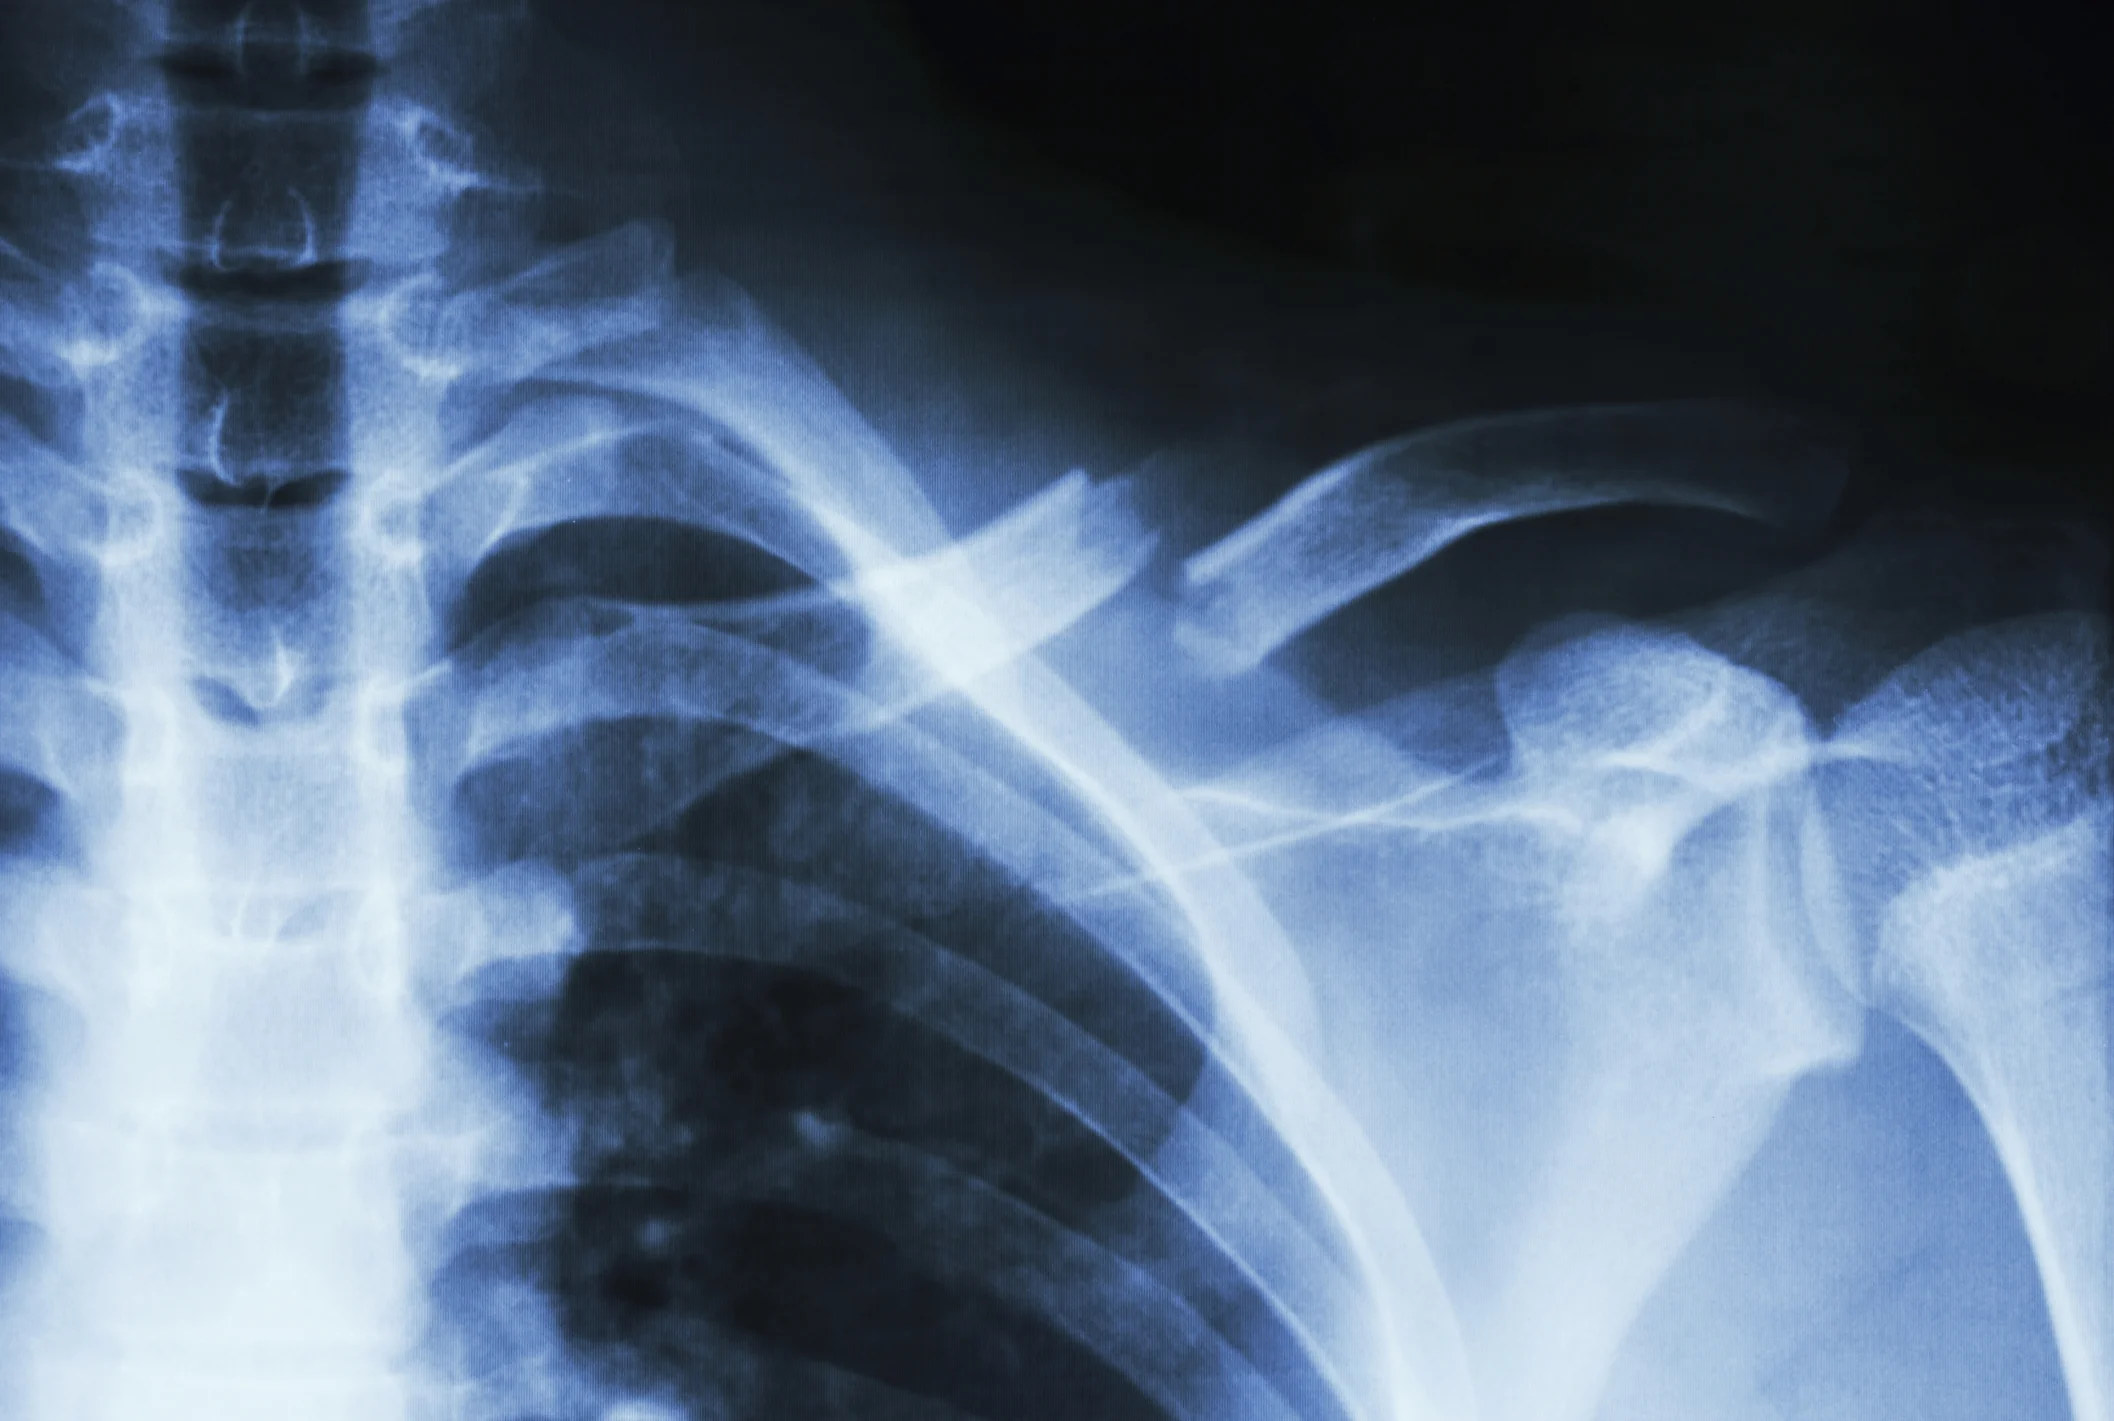

Every year millions of Americans suffer fractures. For elderly people, however every broken bone is serious. Making matters worse, the aging process weakens the bones themselves, as well as the muscles around them. Aging also makes our balance less certain. All this adds up to seniors suffering broken bones at a high percentage relative to the rest of the population - with a more dire impact on their quality of life.

Types of Broken Bones in Elderly Nursing Home Residents

Stress Fractures - Typically, stress fractures are small cracks in the bones that arise from overuse or repetitive action. Often, they are found in the lower body, including especially ankles and feet. Nursing home staff can help prevent stress fractures by carefully monitor the health and well-being of each patient under their care, and by conducting regular consultations.

Compression Fractures - Also known as spontaneous fractures, these injuries occur seemingly out of nowhere. In fact, they are typically the result of deterioration of the bone structure which makes bones more susceptible to fracture. Often, osteoporosis is to blame for these fractures. Everything from getting out of bed to walking can lead to a compression fracture.

Traumatic Fractures - The most familiar form of broken bones, traumatic fractures are caused by impact or injury. Most often, older Americans experience a fall which leads to a traumatic bone break. In terms of liability, nursing homes are responsible for monitoring residents to ensure their safety, in particular they must keep vigilant watch over so-called “fall risk” residents who present a heightened risk of injuring themselves due to age, lack of coordination, or medication.